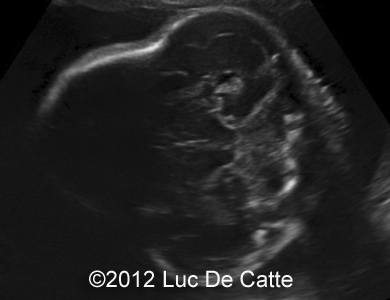

Image 1, 2:  A turricephalic or “tower shaped” skull and frontal bossing

COW_1

COW_1B

• Coronal and sagittal craniosynostosis leading to a turricephalic or “tower shaped” skull

• Prominent forehead (frontal bossing)

• Depressed nasal bridge

• Exophthalmos and prominent open eyelids

• Ocular hypertelorism

• Low -set ears